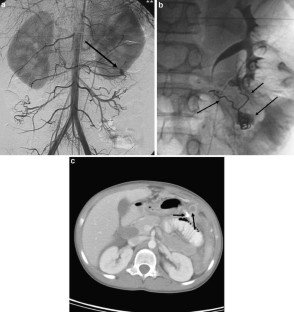

Fig. 3